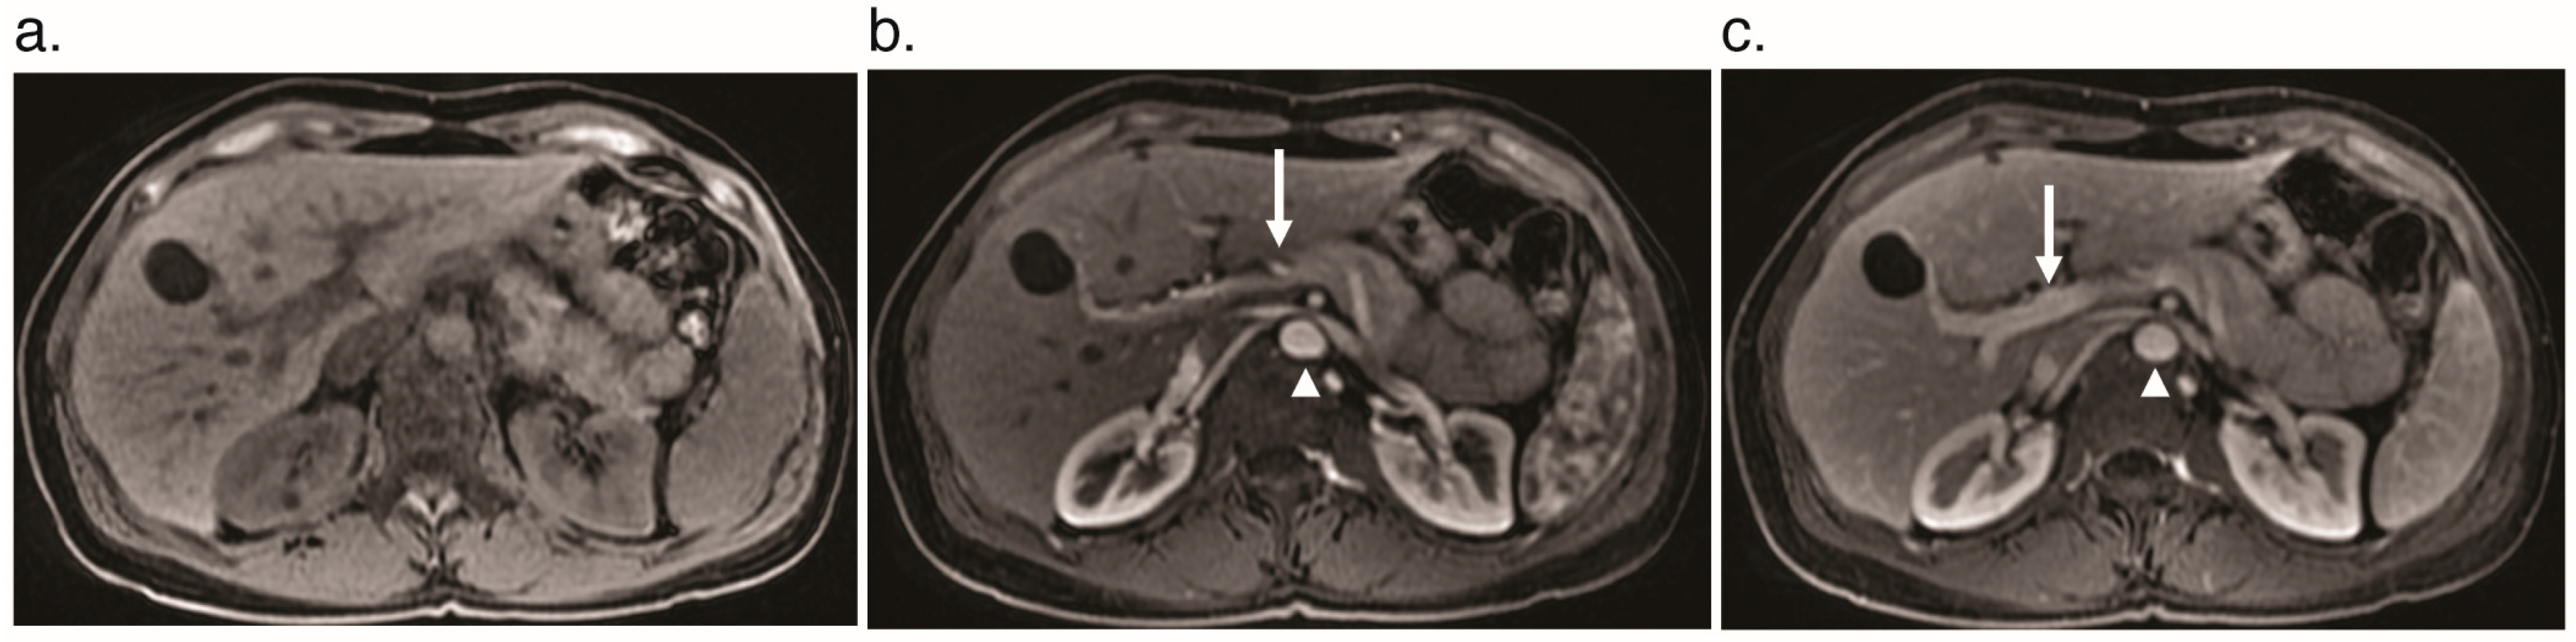

3.1. Arteriosystemic Shunt

3.2. Arterioportal Shunt